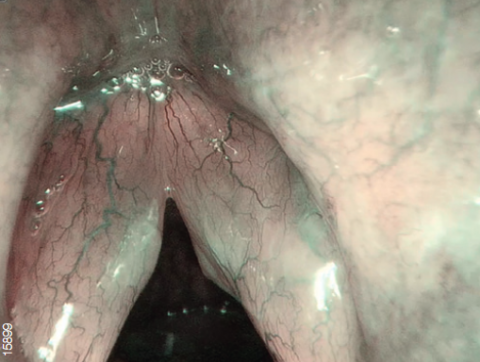

Технология узкоспектральной визуализации изображения NBI

Видеосистема поддерживает режим узкоспектральной визуализации NBI.

NBI - это оптическая технология, которая позволяет визуализировать мельчайшие структуры кровеносных сосудов и слизистой оболочки. В основе технологии лежит принцип поглощения гемоглобином волн определенного спектра (415 и 540 нм). Благодаря уникальным правилам распределения цветов, конечное изображение имеет цветопередачу отличную от обычной.

Свет, попадая в биологическую ткань рассеивается, часть волн (синих и зеленых) поглощается гемоглобином, остальное же распределяется в другие ткани. Поэтому цвет слизистой оболочки желудочно-кишечного тракта в основном определяется гемоглобином. Как упоминалось выше, NBI использует узкополосное освещение с центральной длиной волны 415 и 540 нм. Эти длины волн соответствуют двум пикам поглощения гемоглобина.

Данная технология позволяет с большей точностью визуализировать кровеносные сосуды и слизистую оболочку, а также диагностировать патологические процессы.